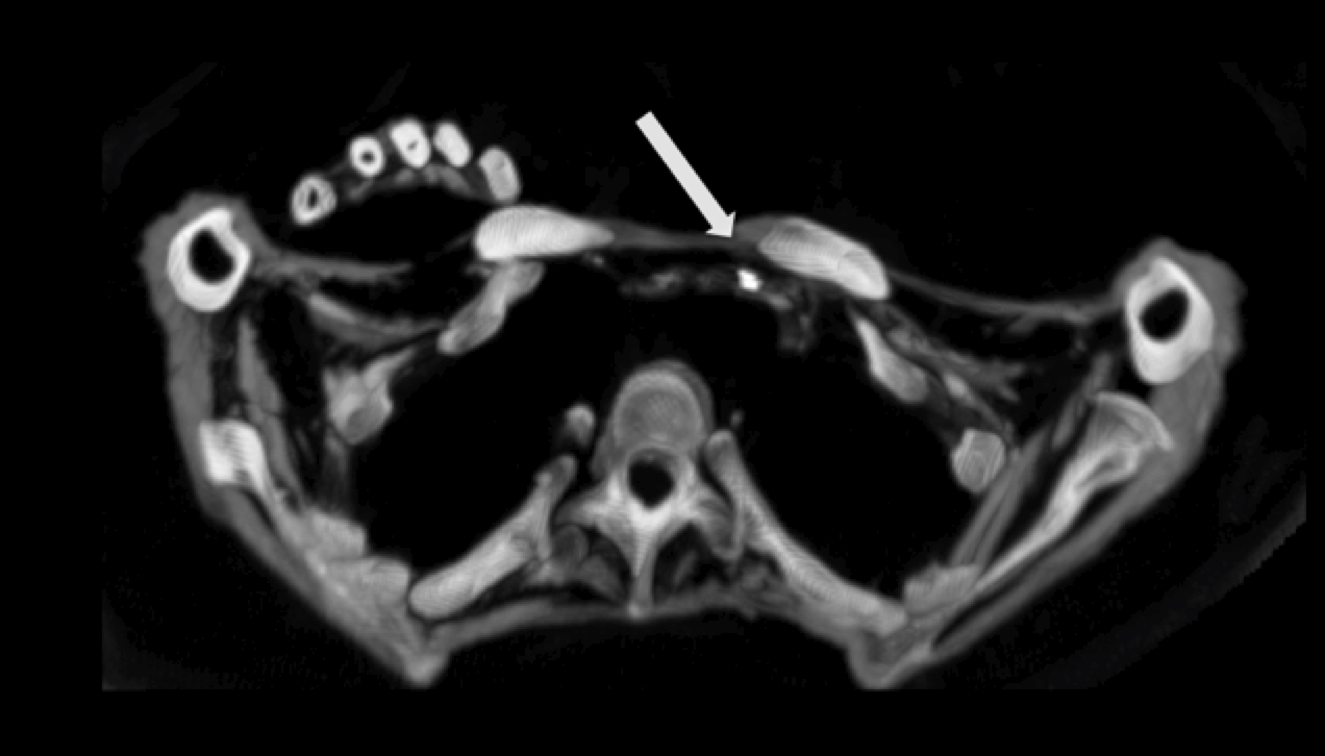

The arrow indicates the superior mesenteric artery. A ct scan allows for more insightful analyses than other imaging tests without the need for invasive over 70 million ct scans are performed in the united states each year, according to research from. Computerized tomography (ct scan) is a procedure that assists in diagnosing tumors, fractures, bony structures, and infections in the organs and tissues of the body. It usually takes approximately 10 to 30 minutes to. Ct scan of the abdomen. What is the difference between ct scan vs mri scan. How do ct scans work? Image slices that ct scans produce can. Ct scans can produce detailed images of many structures inside the body, including the internal organs, blood vessels and bones. The type of ct scan your doctor orders will depend in large part on the area of the body they want to evaluate. Ct scans are most often an outpatient procedure. The person lies on a table that moves through a scanning ring, which looks like a large doughnut. A tumor is visible in the head of the pancreas.

The scan is painless and takes about 10 to 30 minutes. How do ct scans work? It is often the choice of examination basic principles. The arrow indicates the superior mesenteric artery. The person lies on a table that moves through a scanning ring, which looks like a large doughnut. Ct scans are most often an outpatient procedure. Ct scans are used to image a wide variety of body structures and internal organs. The type of ct scan your doctor orders will depend in large part on the area of the body they want to evaluate. A ct scan allows for more insightful analyses than other imaging tests without the need for invasive over 70 million ct scans are performed in the united states each year, according to research from. It usually takes approximately 10 to 30 minutes to. Ct scans of the abdomen may also be used to visualize placement of needles during biopsies of abdominal organs or tumors or during aspiration (withdrawal) of fluid from the abdomen. The procedure is also known as. This provides a series of images from many different angles.

The arrow indicates the superior mesenteric artery ct scan. How do ct scans work?